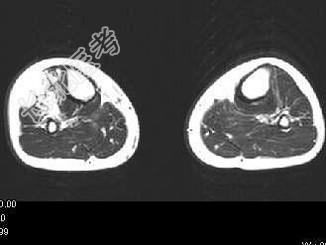

- 单项选择题男,15岁, 小时候发现左下肢肿胀,曾多次出血, 结合图像,最可能的诊断是 ( )

C、下肢血管瘤